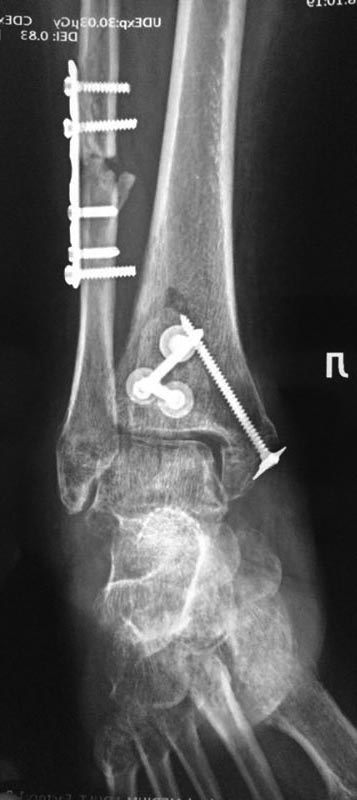

После остеосинтеза лодыжек |

А вот такую задачку нам задали друзья с севера. Операция в мае этого года. На данный момент пациент опереться на конечность не может.

Возраст: за 50. Движений в голеностопном суставе практически нет ( в пределах 10-15 градусов) суставы стопы функционируют. Умеренная контрактура. Ходит с костылями, приступает на ногу. Нагрузка не по оси. Внешний вид: застарелый отек.

Да, и забыл отметить. Обратите внимание на синтез заднего края. Доступ с отсечением ахилла